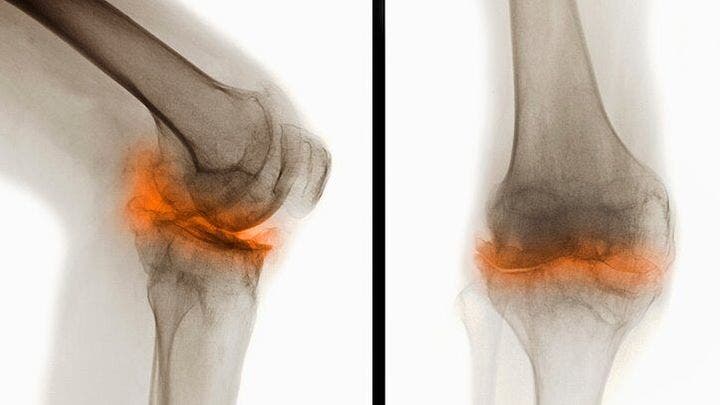

4.Elle soulage les douleurs articulaires

Durant le processus de la marche, le muscle se renforce et se lubrifie au gré de l’effort fourni. Et c’est la raison pour laquelle vos genoux et vos hanches sont alors d’autant plus soutenus.

Par ailleurs, le fait de marcher s’avère bénéfique pour les personnes atteintes d’arthrite dont les douleurs articulaires sont réduites. De plus, cela participe aussi à la prévention de l’arthrite pourvu que les séances atteignent les 8 à 9 km par semaine comme le suggère l’université d’Harvard.